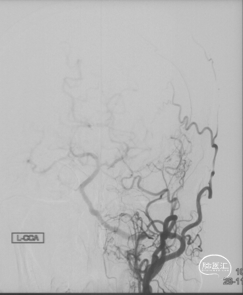

CTA和DSA

CTA和DSA所见:双侧颈内动脉闭塞,右侧椎动脉发出PICA后闭塞,左侧椎动脉V1-V2段闭塞。两条健壮的侧枝通过肌支吻合汇入左椎动脉V2段,构成了整个大脑大部分供血的主要来源。双侧颈外动脉亦有少量血流供应颅内。这样的颅内供血很容易发生失代偿,导致TIA甚至脑梗。